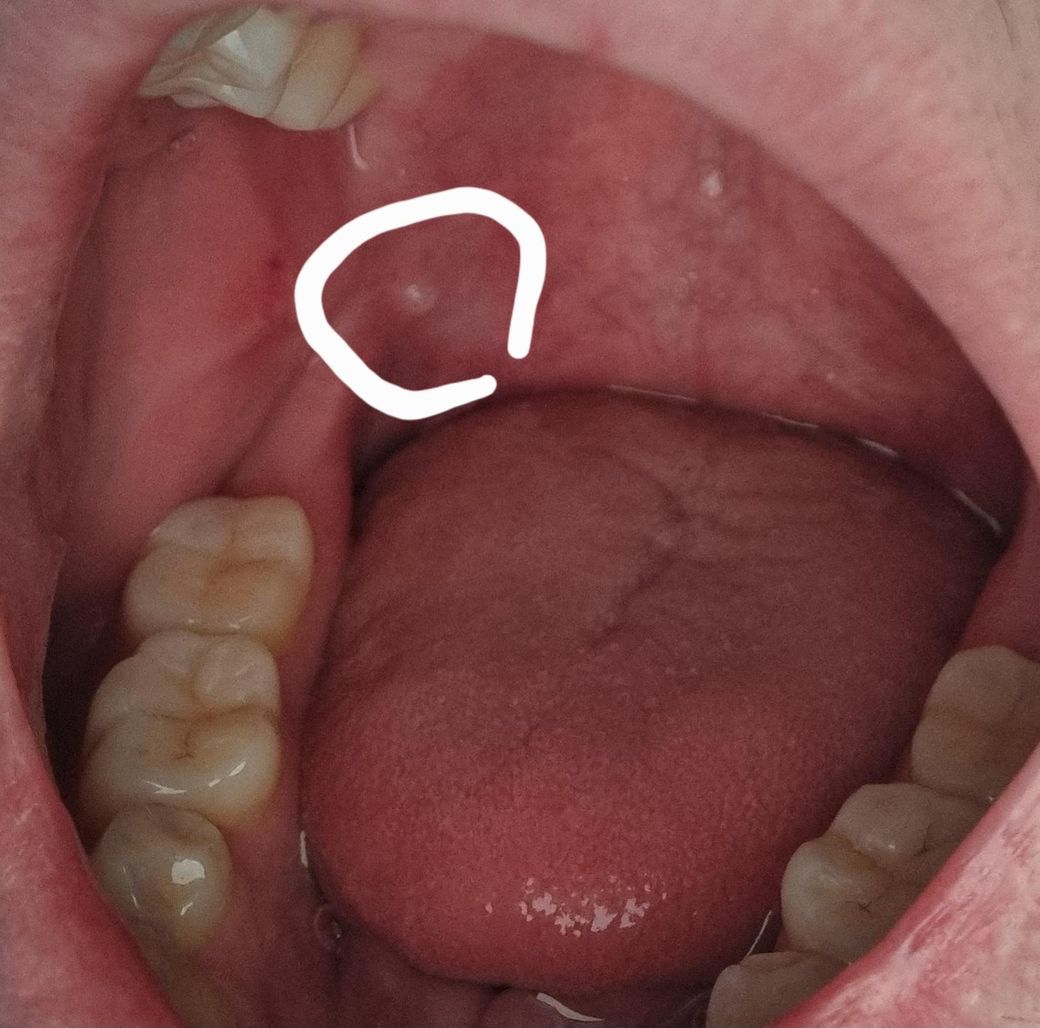

사진처럼 저렇게 혹같은게 생겼는데 저게 뭔가요?

혀로 닿으면 느낌이 이상하긴하네요 그냥 피곤해서 그런가보다 싶었는데 뭔가 찜찜해서 질문남겨봅니다...

단순 지방종일 가능성이 높아 보이나 정확한 판단을 위해서는 구강내과를 방문하여 검사를 한 번 받아보는 것이 좋습니다. 지금 상태에서 더 커지거나 혹시나 불편감 등이 갑자기 나타난다면 지체하지 마시고 바로 치과를 방문하는 것이 필요해보입니다. 모양이나 색으로 보았을 때 크게 문제가 있는 것으로 보이지는 않습니다.

사진 흐려 명확히 보이지는 않으나 소타액선 저류로 발생한 점액류로 추정됩니다. 해당부위 크기 작은 상태로 지켜보시다가 크기 변화 있을 시 구강악안면외과 등 내원하시는 것 권유드립니다.